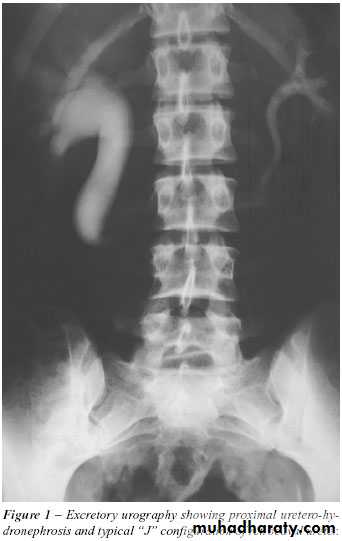

*PUJ obstruction